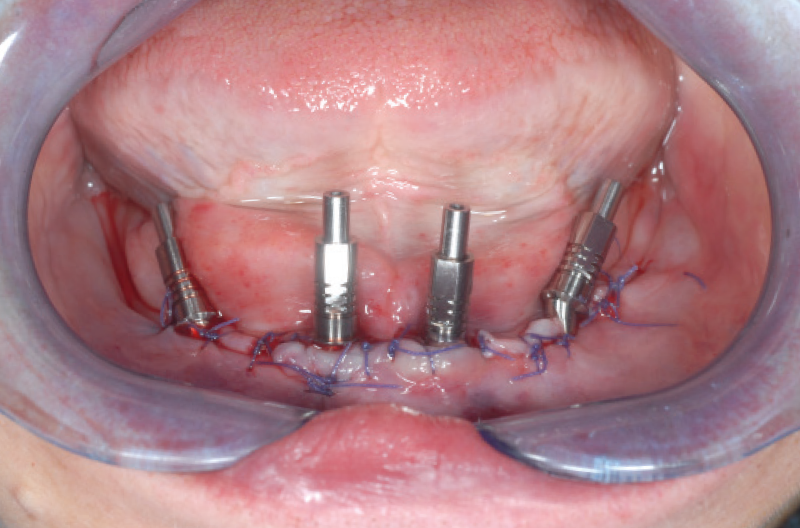

L’intervento si svolge in sedazione cosciente, facilitando le manovre chirurgiche e alleggerendo l’impatto sulla paziente. Prima di tutto si effettua un lembo a tutto spessore della dimensione sufficiente per accogliere la dima chirurgica ad appoggio osseo. In questo caso sono state realizzate due dime: la prima viene utilizzata per regolarizzare la cresta ossea che risulta molto sottile, mentre la seconda, che sfrutta lo stesso pin della prima per il fissaggio, viene usata per la preparazione dei siti implantari. Si posizionano due impianti distali XCN® Classix Ø 3,3 x 12 mm e due impianti centrali XCN® Classix Ø 3,3 x 10 mm (Figg. 13-16).

Una volta inseriti gli impianti, vengono selezionati e posizionati i monconi MUA più idonei per altezza e angolazione, andando a ricercare la posizione più distale possibile ed evitando di creare un eccessivo cantilever che potrebbe compromettere il successo del carico immediato. Per fissare i cilindri da saldatura sui monconi MUA si usano le viti polifunzionali per preservare il canale della vite durante la saldatura (Figg. 17, 18).

Fig. 17 – Monconi MUA attivati negli impianti